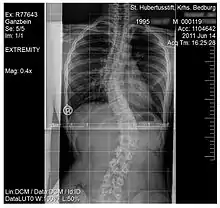

Scoliosis

Scoliosis, is a medical condition where a person's spine has several irregular curves that are located between the neck and the pelvis.[8] Symptoms of scoliosis in mild cases usually exhibit abnormal posture, back pain, tingling or numbness in the legs and in worse cases can exhibit breathing problems, fatigue, permanent deformities and in rare cases heart problems.[8]